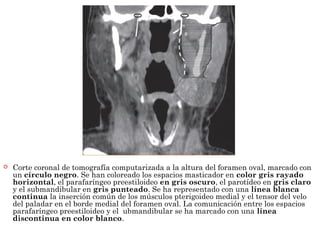

 Corte coronal de tomografía computarizada a la altura del foramen oval, marcado con

un círculo negro. Se han coloreado los espacios masticador en color gris rayado

horizontal, el parafaríngeo preestiloideo en gris oscuro, el parotídeo en gris claro

y el submandibular en gris punteado. Se ha representado con una línea blanca

continua la inserción común de los músculos pterigoideo medial y el tensor del velo

del paladar en el borde medial del foramen oval. La comunicación entre los espacios

parafaríngeo preestiloideo y el ubmandibular se ha marcado con una línea

discontinua en color blanco.

 Corte coronalde tomografía computarizada a la altura del foramen oval, marcado con un círculo negro. Se han coloreado los espacios masticador en color gris rayado horizontal, el parafaríngeo preestiloideo en gris oscuro, el parotídeo en gris claro y el submandibular en gris punteado. Se ha representado con una línea blanca continua la inserción común de los músculos pterigoideo medial y el tensor del velo del paladar en el borde medial del foramen oval. La comunicación entre los espacios parafaríngeo preestiloideo y el ubmandibular se ha marcado con una línea discontinua en color blanco.